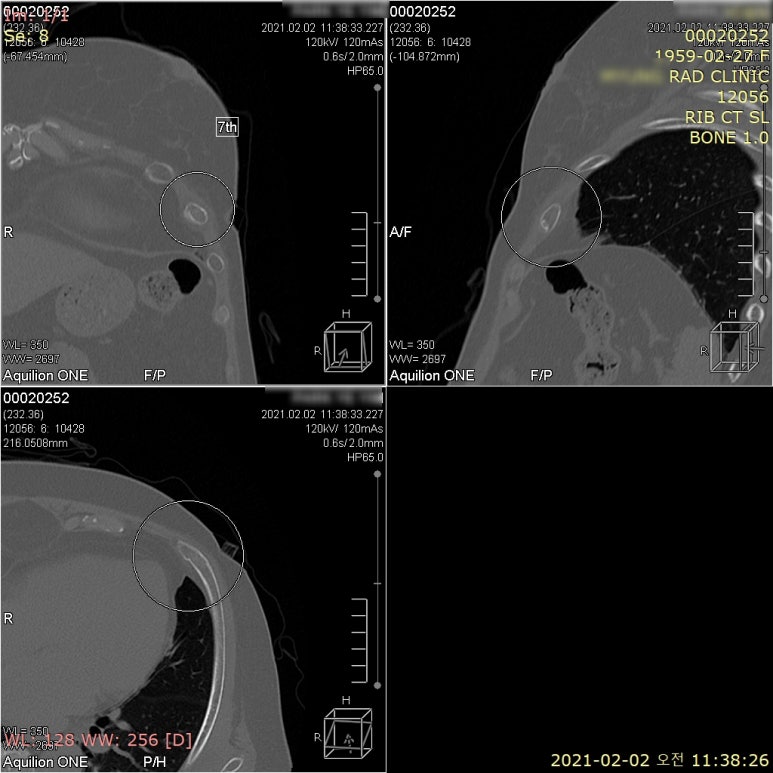

구형 CT 검사기에서는

슬라이스 간격이 넓기 때문에

2mm 이하의

작은 미세골절은 안보이기도 합니다.

최근에는 기술이 좋아지면서

검사시간이 짧고

방사선 노출이 적은

저선량 CT로

검사하는 추세입니다.

최신 640 CT는

과거에 사용하던

64 or 128 슬라이스 CT와 달리

0.5mm 간격으로

640장의 영상을 얻으면서

기존 CT의 10%에

해당하는 저선량으로

인체 친화적 검사기입니다.

늑골 골절에서

본래 위치를 벗어나

폐를 찌르게 되면

기흉, 혈흉이 동반되는 경우도

있기 때문에

세밀한 검사를 위해

본원에서는 640CT로

의뢰하고 있습니다.